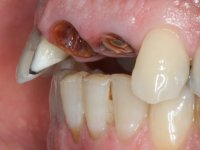

Patient male, 60 years old, non-smoker. After imaging and clinical examination, it was found that the patient had teeth 2.1 and 2.2 with extensive acrylic restorations, with screwed intra radicular posts and very poor endodontic treatments. Tooth 2.2 had an extensive apical lesion, the post had been placed on a false route and had mobility. Tooth 1.1 had an extensive resine restoration and tooth 1.2 presented a mesial restoration, also in composite resin, Class III type. The antero-superior sector was vestibularized, as consequence of a loss of vertical occlusion dimension associated with posterior edentulism. The patient showed reasonable periodontal health and satisfactory oral hygiene.

Endodontic treatments were performed and a metalic non screwed intra radicular post was placed on tooth 1.1. An alginate impression was made for laboratory confection of a reinforced acrylic provisional bridge, with teeth 1.1 and 2.2 as abutments and 2.2 as a pontic. After preparation of tooth 1.1 and root preparation of 2.1, the bridge was relined in mouth with self-polymerizable acrylic using a metal post for further retaining the prepared root canal on 2.1. Tooth 2.2 was cut at the gingival level to function as support. In the same session, the impression of the root canal of the 2.1 was made for the laboratory confection of a cast post and core. A double mixture technique with plastic tutor was used after previous canal vaseline with endodontic file and cotton. The provisional bridge was provisionally cemented and the cast post and core was made in the laboratory. Cast post and core cementation was made with resin-reinforced glass ionomer cement and the provisional bridge had to be readjusted to the new situation by removing the post at the site of 2.1. After careful surgical planning, a dental implant was placed, simultaneously with extraction of the root of tooth 2.2. The provisional bridge was placed by resting on the healing screw placed in the implant. The respected osteointegration period was 12 weeks, during which the provisional bridge was relined twice. After complete maturation of hard and soft tissues, definitive impressions were made. The gingival retraction technique was applied with an impregnated retraction cord and impression was performed using double mixture, open tray impression technique. A custom precious metal abutment implant was prepared in the lab, along with 3 metal caps to be used as infrastructures for the metal ceramic crowns. Particular care was taken in the confection of the cervical finishing line of the implant abutment, in order to follow the soft tissues emergence profile. Proof of infrastructures was done in the mouth being evaluated clinically and imagiologically. Collection of color information was done by the ceramist at the office. Ceramic was applied in the laboratory and the finished work was placed in the mouth after approval by the patient. Definitive cementation was made with resin-reinforced glass ionomer cement, and the first crown to be cemented was that of the implant, to facilitate removal of the excess.